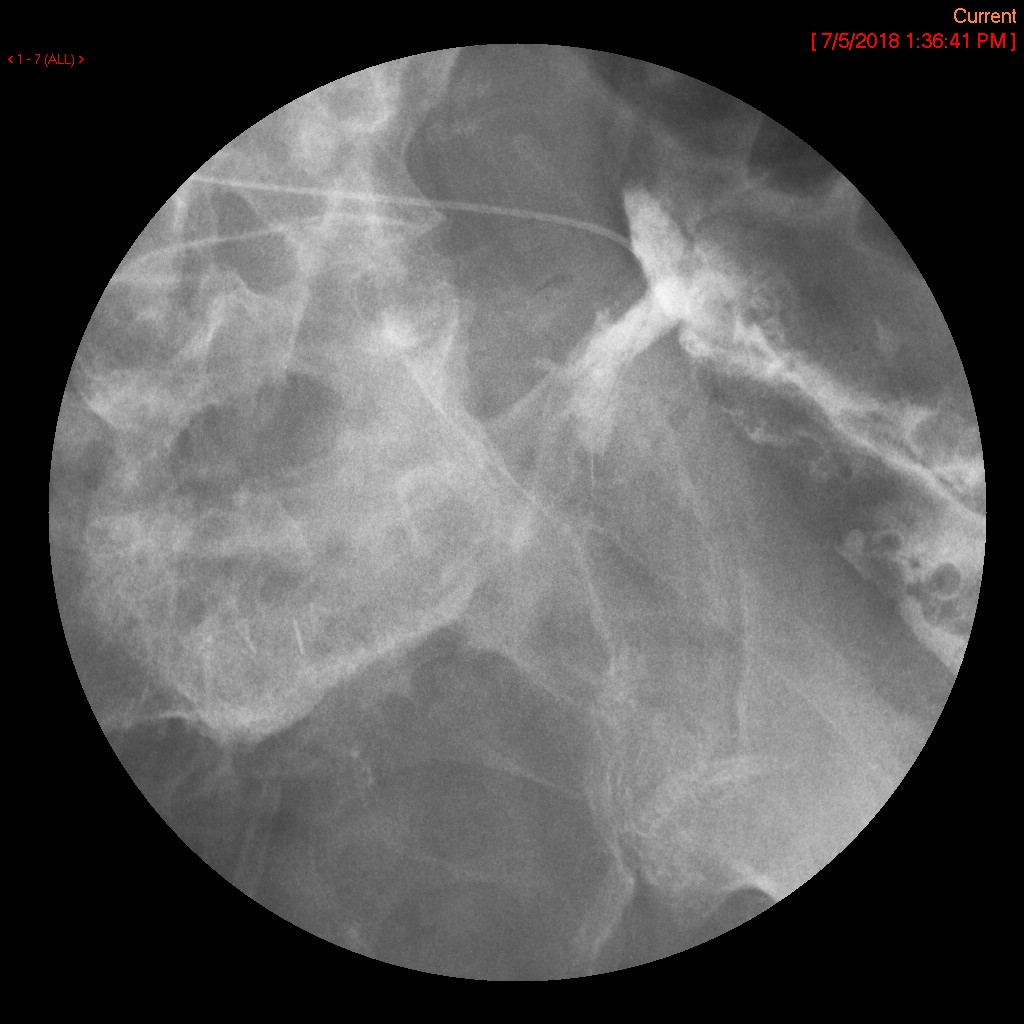

- Once the barium has reached the small bowel, you will go into the room and obtain spot images of the contrast material filled small bowel.

- Obtain images of the terminal ileum and the ileocecal valve filled with contrast material

(key image 6)

(key image 7)

(key image 8)

(key image 9)

(key image 10).

- Obtain spot images of the remainder of the small bowel

(key image 11)

(key image 12)

(key image 13)

(key image 14).

- Obtain images of all four quadrants. Use the compression paddle to separate loops of small bowel from each other.

- Evaluate for tethering of small bowel to any other structures.

- Observe for small bowel peristalsis.